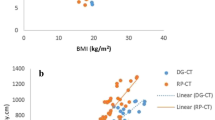

There was a significant positive correlation between DAP value and body weight (Fig. 3A; r = 0.76, slope 0.238 Gycm2/kg, p < 0.001) as well as ED and body weight (Fig. 3B; r = 0.55, slope = 0.045 mSv/kg, p < 0.001). The conversion factor ED per DAP decreased with increasing body weight (Fig. 3C; r = 0.99, slope = −0.00279 mSv/Gycm2kg, p < 0.001 for upper abdominal CBCT and r = 0.99 slope = −0.00197 mSv/Gycm2kg, p < 0.001 for lower abdominal CBCT). Adding patients’ body height as an independent variable into the regression models yielded no significant regression coefficients for height (p > 0.05).